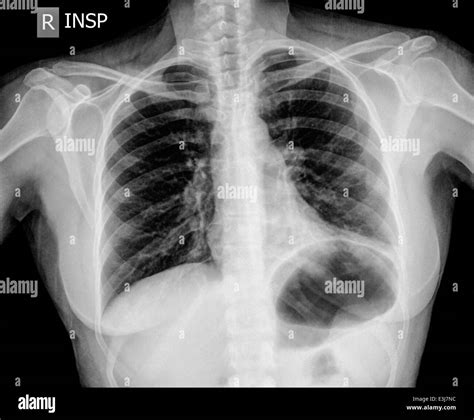

Chest X Ray Symptoms – Chest X Ray Medical – OVNI is a high-quality image in the Cleve collection, available at 1300 × 1154 pixels resolution — ideal for both digital and print use.

Learn to identify common chest X-ray abnormalities with this comprehensive guide. We break down key findings, including pulmonary opacities, pleural effusions, and cardiomegaly. Improve your diagnostic accuracy by understanding how to interpret thoracic imaging, recognize clinical patterns, and distinguish between normal anatomy and pathological signs in routine chest radiography for better patient management and improved clinical outcomes.